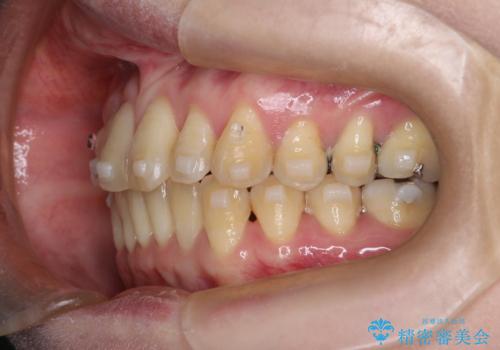

- 上の前歯の捻れと、前歯で物が噛めないことを主訴に来院されました。

前歯の翼状捻転とオープンバイト傾向だったため、インビザラインにて矯正を行いました。右下の奥歯は保存不可だったため、抜歯を行いインプラントにて修復を行なっています。

翼状捻転はインビザラインでは苦手とする動きですが、ここまで綺麗に治すことができました。